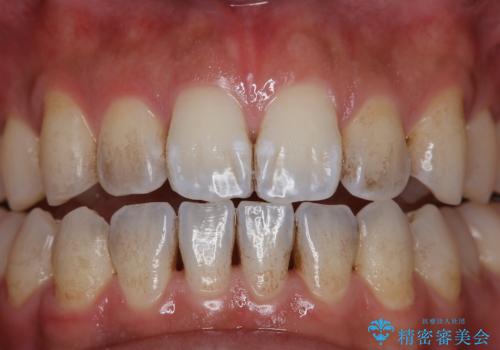

- コーヒーを毎日飲むため、歯が黒くなり気になるとのことでした。

また、以前他院にて矯正治療を行い、前歯の裏側には保定装置がついていることで磨きにくいため機械的に細かい部分のクリーニングも希望とのことでした。

コーヒーによる歯の着色の原因

歯の表面は『ペリクル』と言われる被膜で覆われています。

そのペリクルはエナメル質を保護する働きや、再石灰化を促す働きがあります。

コーヒーの中には、ポリフェノールが含まれていますが、ポリフェノールとペリクルが結合すると色素沈着を起こします。